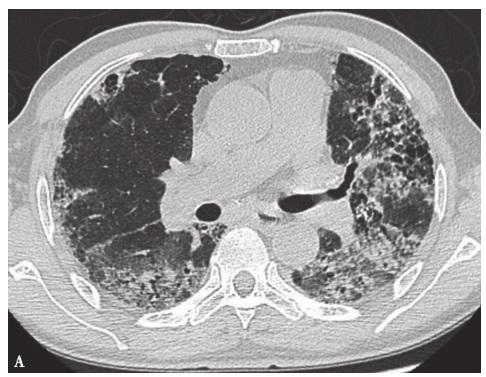

1小时条评论48岁男性患者,5个月前出现咳嗽,多为干咳,偶有少量白痰咳出,起初无明显气喘,间断至当地医院予青霉素等抗感染治疗,效果不佳。1个月前,患者自觉咳嗽症状加重,并出现活动后气喘,上二层楼即感气喘,于当地医院住院诊治,查胸部CT示双肺弥漫性病变。患者在机械厂...